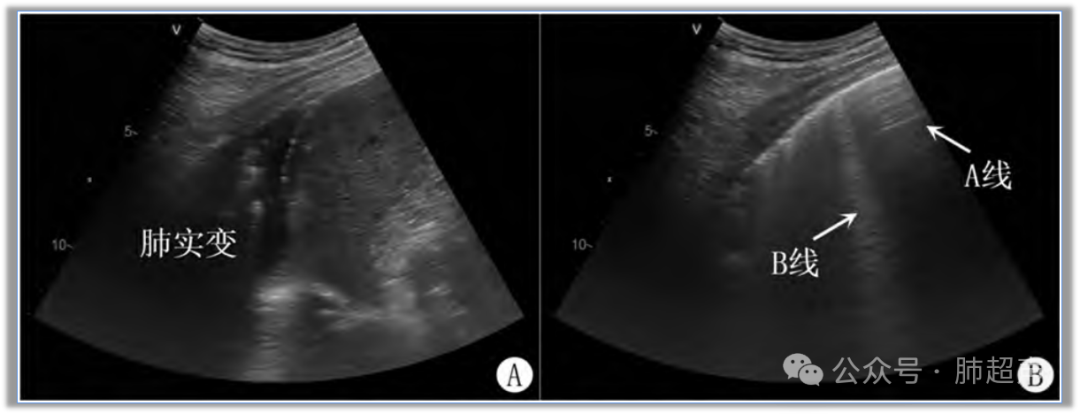

肺实变随吸气可转换为B线或A线 (图1),系因气体含量增加导致肺超声征象发生变化,提示该区肺支气管—肺泡气道通畅,肺泡存在充气复张潜能,可排除阻塞性肺不张。

图1  吸气过程诱发肺超声气—液往返征示意图

注:A. 呼气末; B. 吸气末